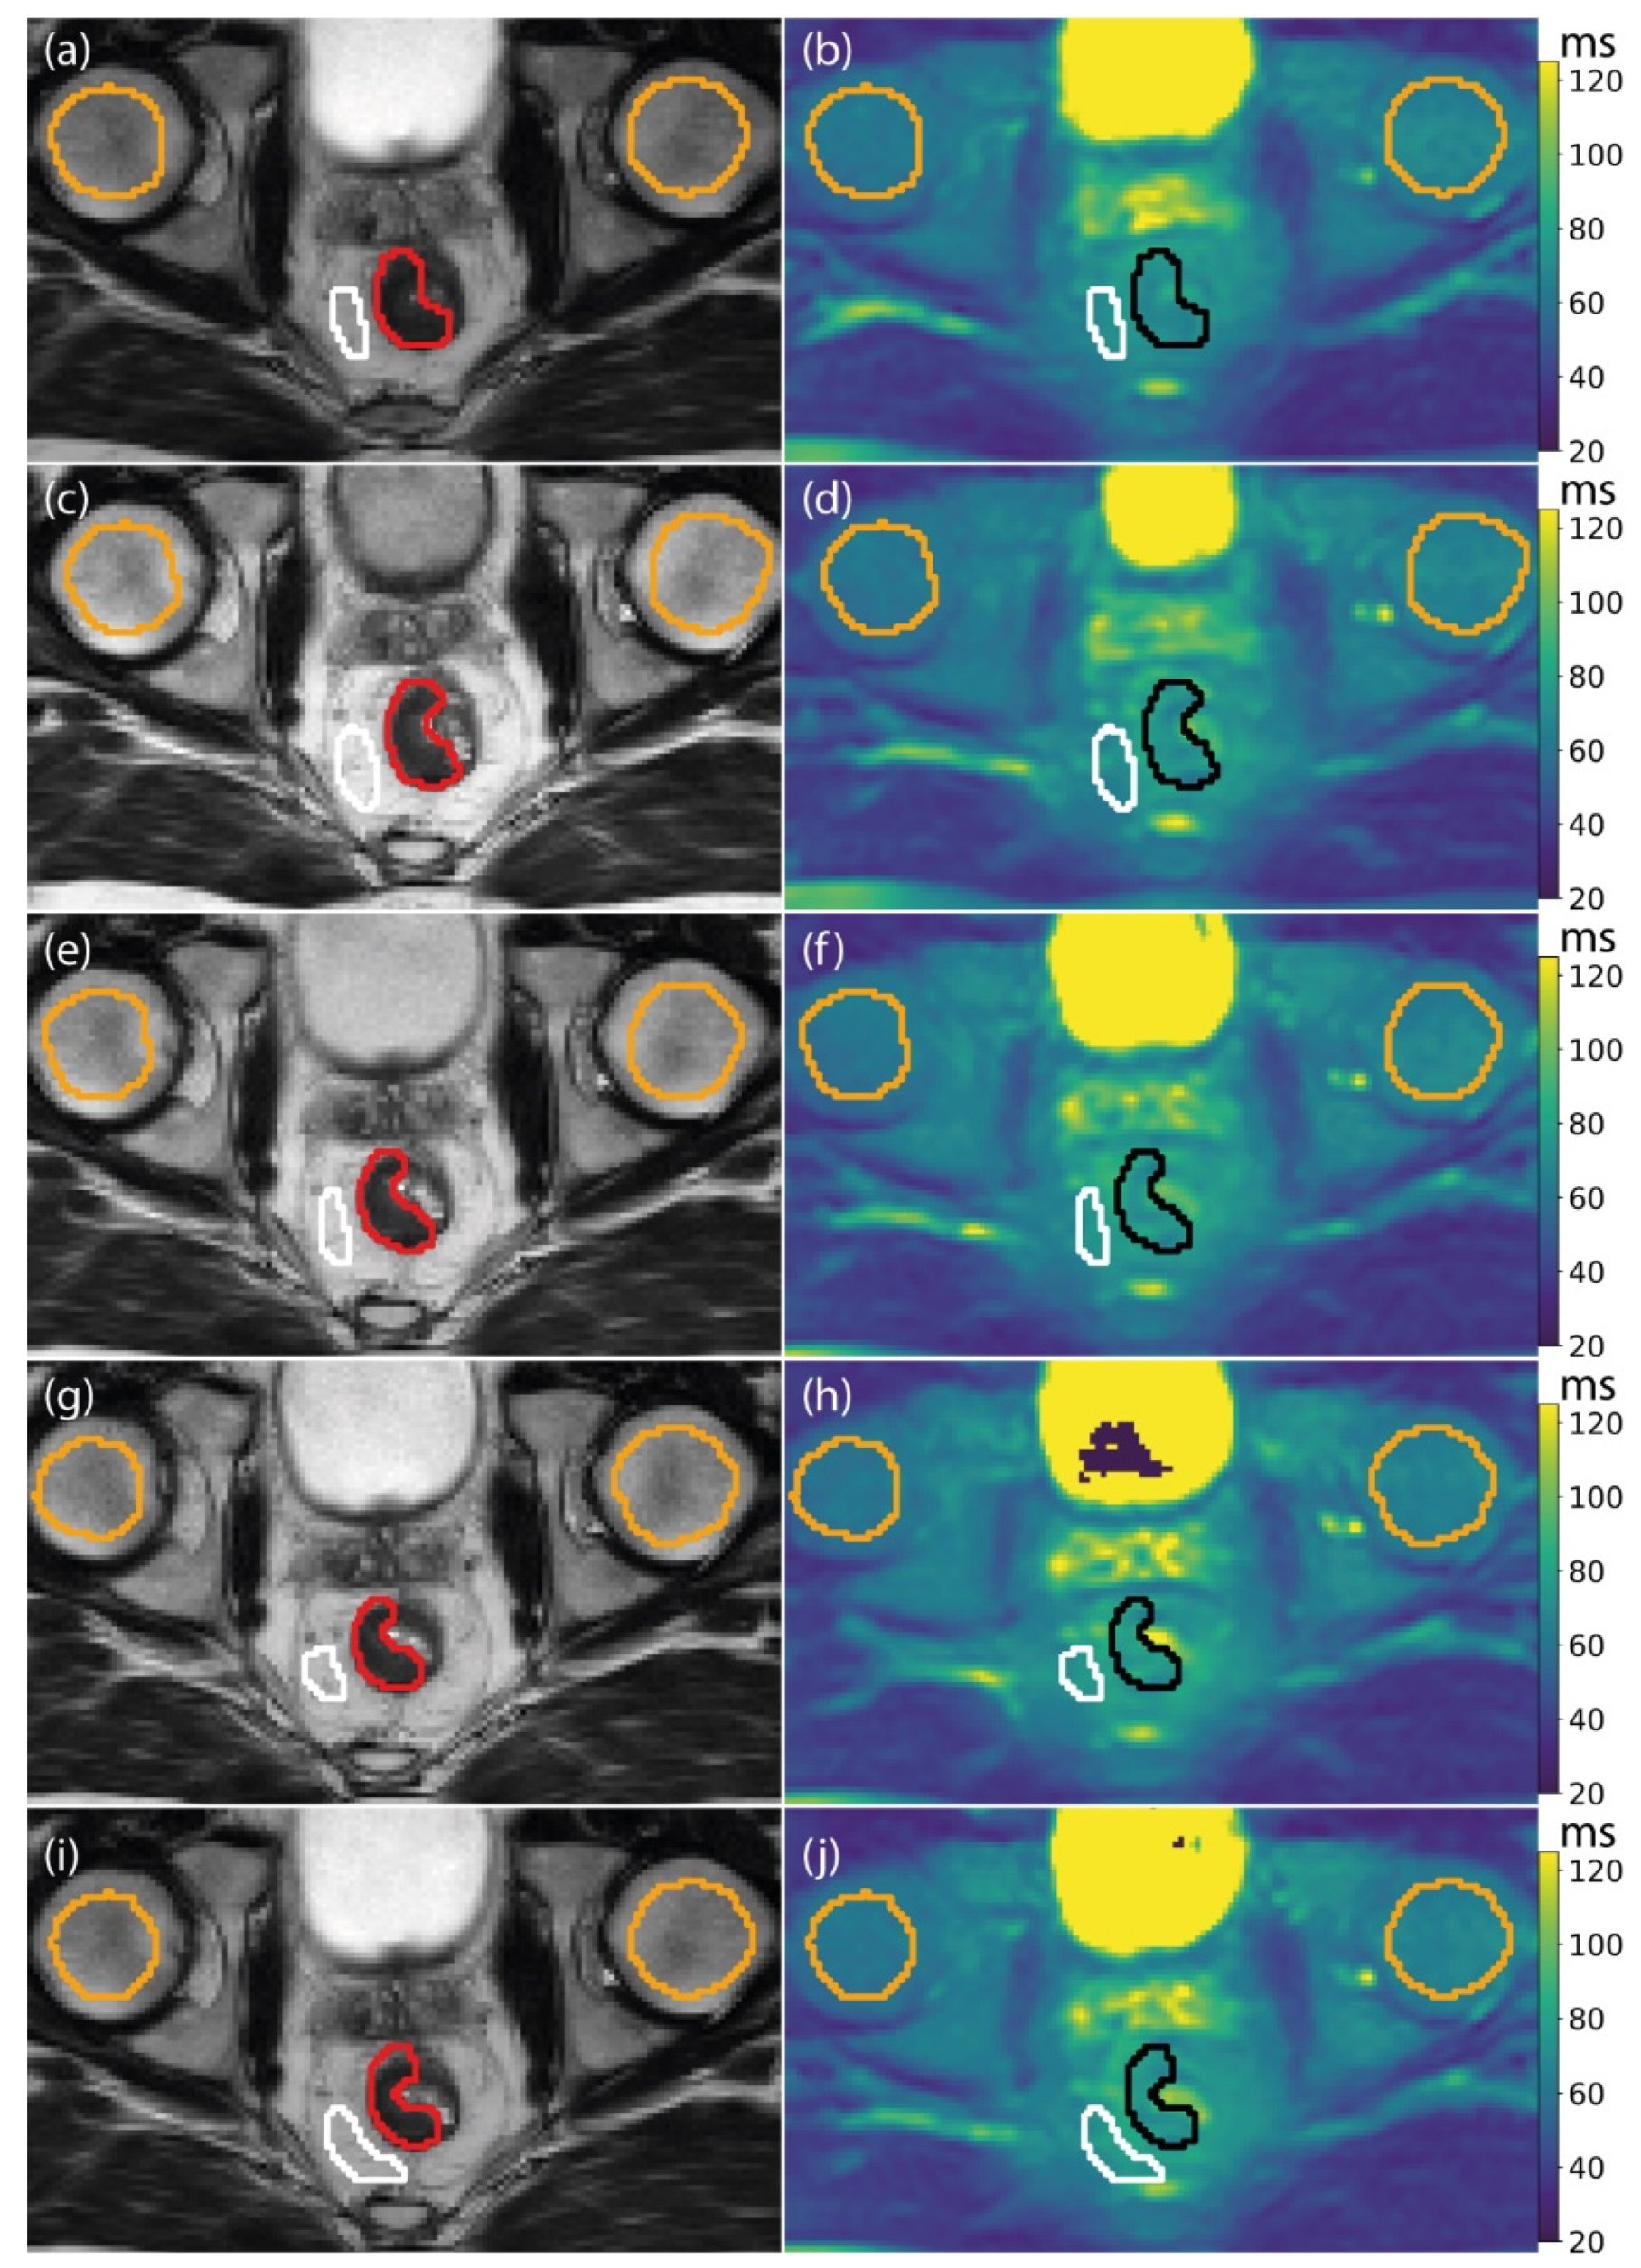

All 12 patients were successfully scanned at each treatment fraction for a total of 60 fractions. An example T1ρ map from all the fractions of a single patient is shown in Figure 2.

Figure 2.

Example T1ρ maps of a single patient. Each row corresponds to a different treatment fraction. On the left, (a,c,e,g,i) the T2-weighted image used for delineation is shown, with the corresponding T1ρ maps on the right (b,d,f,h,j). The gross tumor volume (GTV) is shown in red on the T2-weighted image and in black on the T1ρ image. The mesorectum region of interest (ROI) is shown in white, and the femoral heads are shown in orange. The T1ρ maps are shown on a color scale from 20 to 120 ms.

Baseline T1ρ values, measured on the first fraction before receiving the first radiation dose, were 77 ± 8 ms (mean ± SD of all patients) for the GTV; 73 ± 11 ms for the mesorectum; 64 ± 4 ms for the left femoral head; and 59 ± 5 ms for the right femoral head. The RC in both femoral heads was 4 ms.